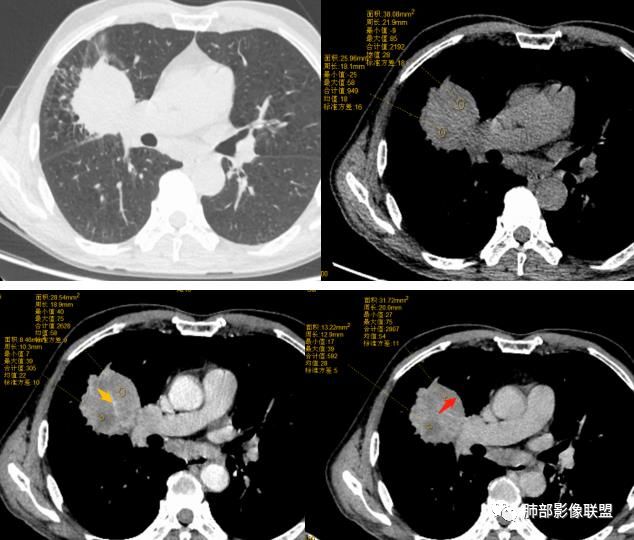

患者中老年男性,体检发现右肺占位。血常规轻度贫血,AFP、CEA正常,肝肾功能、血糖、血脂、心肌酶、电解质正常。胸部CT:右肺中叶巨大肿块灶,垮叶生长,可见分叶、毛刺、血管集束、支气管截断征象,远端周围可见小叶间隔增厚,增强轻度强化,内可见低密度坏死区,综合淋巴结肿大,且可见淋巴结内似低密度灶。综合考虑恶性,鳞癌并癌性淋巴管炎可能大。鉴别结核、腺癌。

患者中老年男性,体检发现肺部占位。

胸CT:右肺中叶团块样实性占位,边缘膨隆,中叶外侧段阻塞,病灶可见深分叶、棘突,胸膜牵拉;增强不均匀强化,可见边缘模糊血管影,病灶内大片状低密度区,纵隔多发肿大淋巴结。

诊断考虑:恶性病变,鳞?大细胞?鉴别:TB